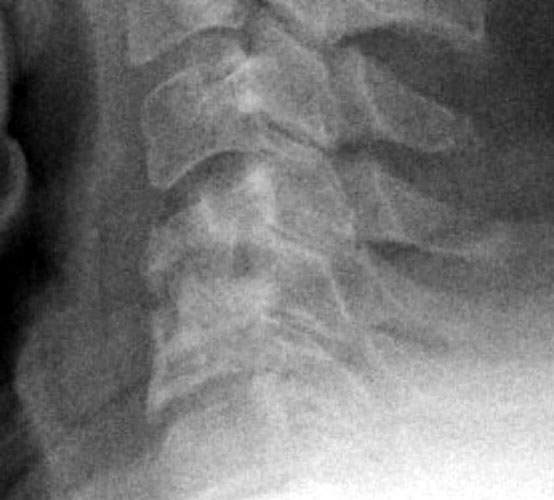

8 months later, the follow-up films demonstrate lucency at the

graft site worrisome for resorption. Figure _. Axial CT examination, without

contrast. |